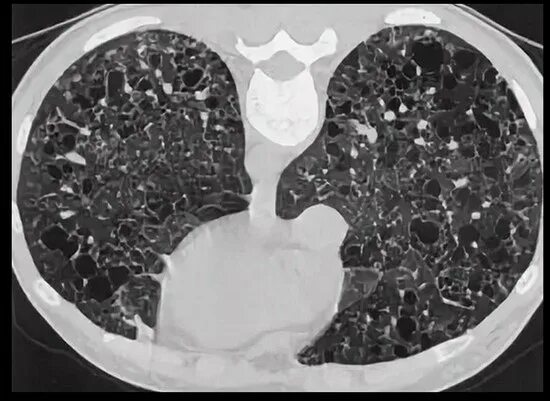

Фиброз кт